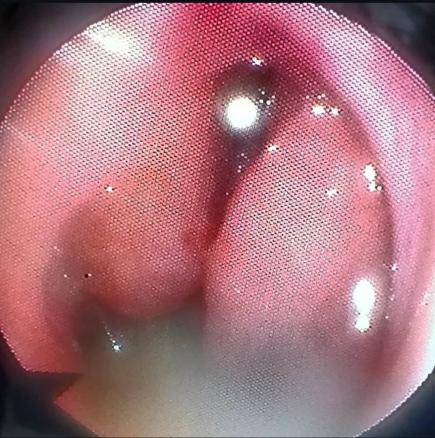

Une patiente âgée de 40 ans est admise à l’hôpital pour exploration d’adénopathies cervicales. L’interrogatoire révèle une obstruction nasale chronique accompagnée d’une rhinorrhée. L’endoscopie met en évidence une rhinite croûteuse avec un bombement du cavum (fig. 1). La tomodensitométrie montre un cavum pseudotumoral (fig. 2, 3 et 4). L’histologie objective un processus granulomateux tuberculoïde (fig. 5). Le GeneXpert sur fragment de biopsie, l’intradermoréaction à la tuberculine et la recherche de bacille de Koch dans les crachats sont négatifs.